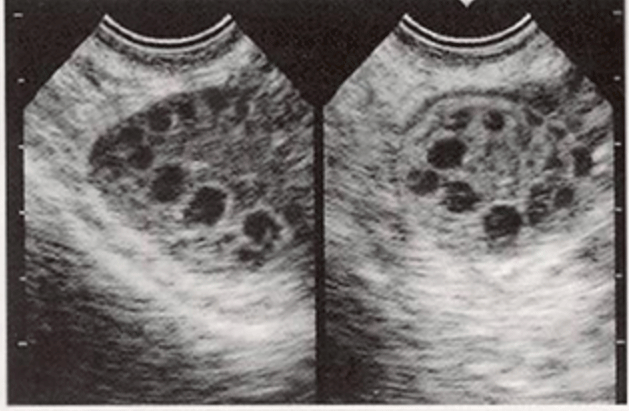

- 초음파 검사 : 질식 초음파를 통해 난소의 상태를 확인하고, 다낭성 난소의 소견을 관찰합니다. 생리 주기가 불규칙한 여성에서 자주 시행됩니다.